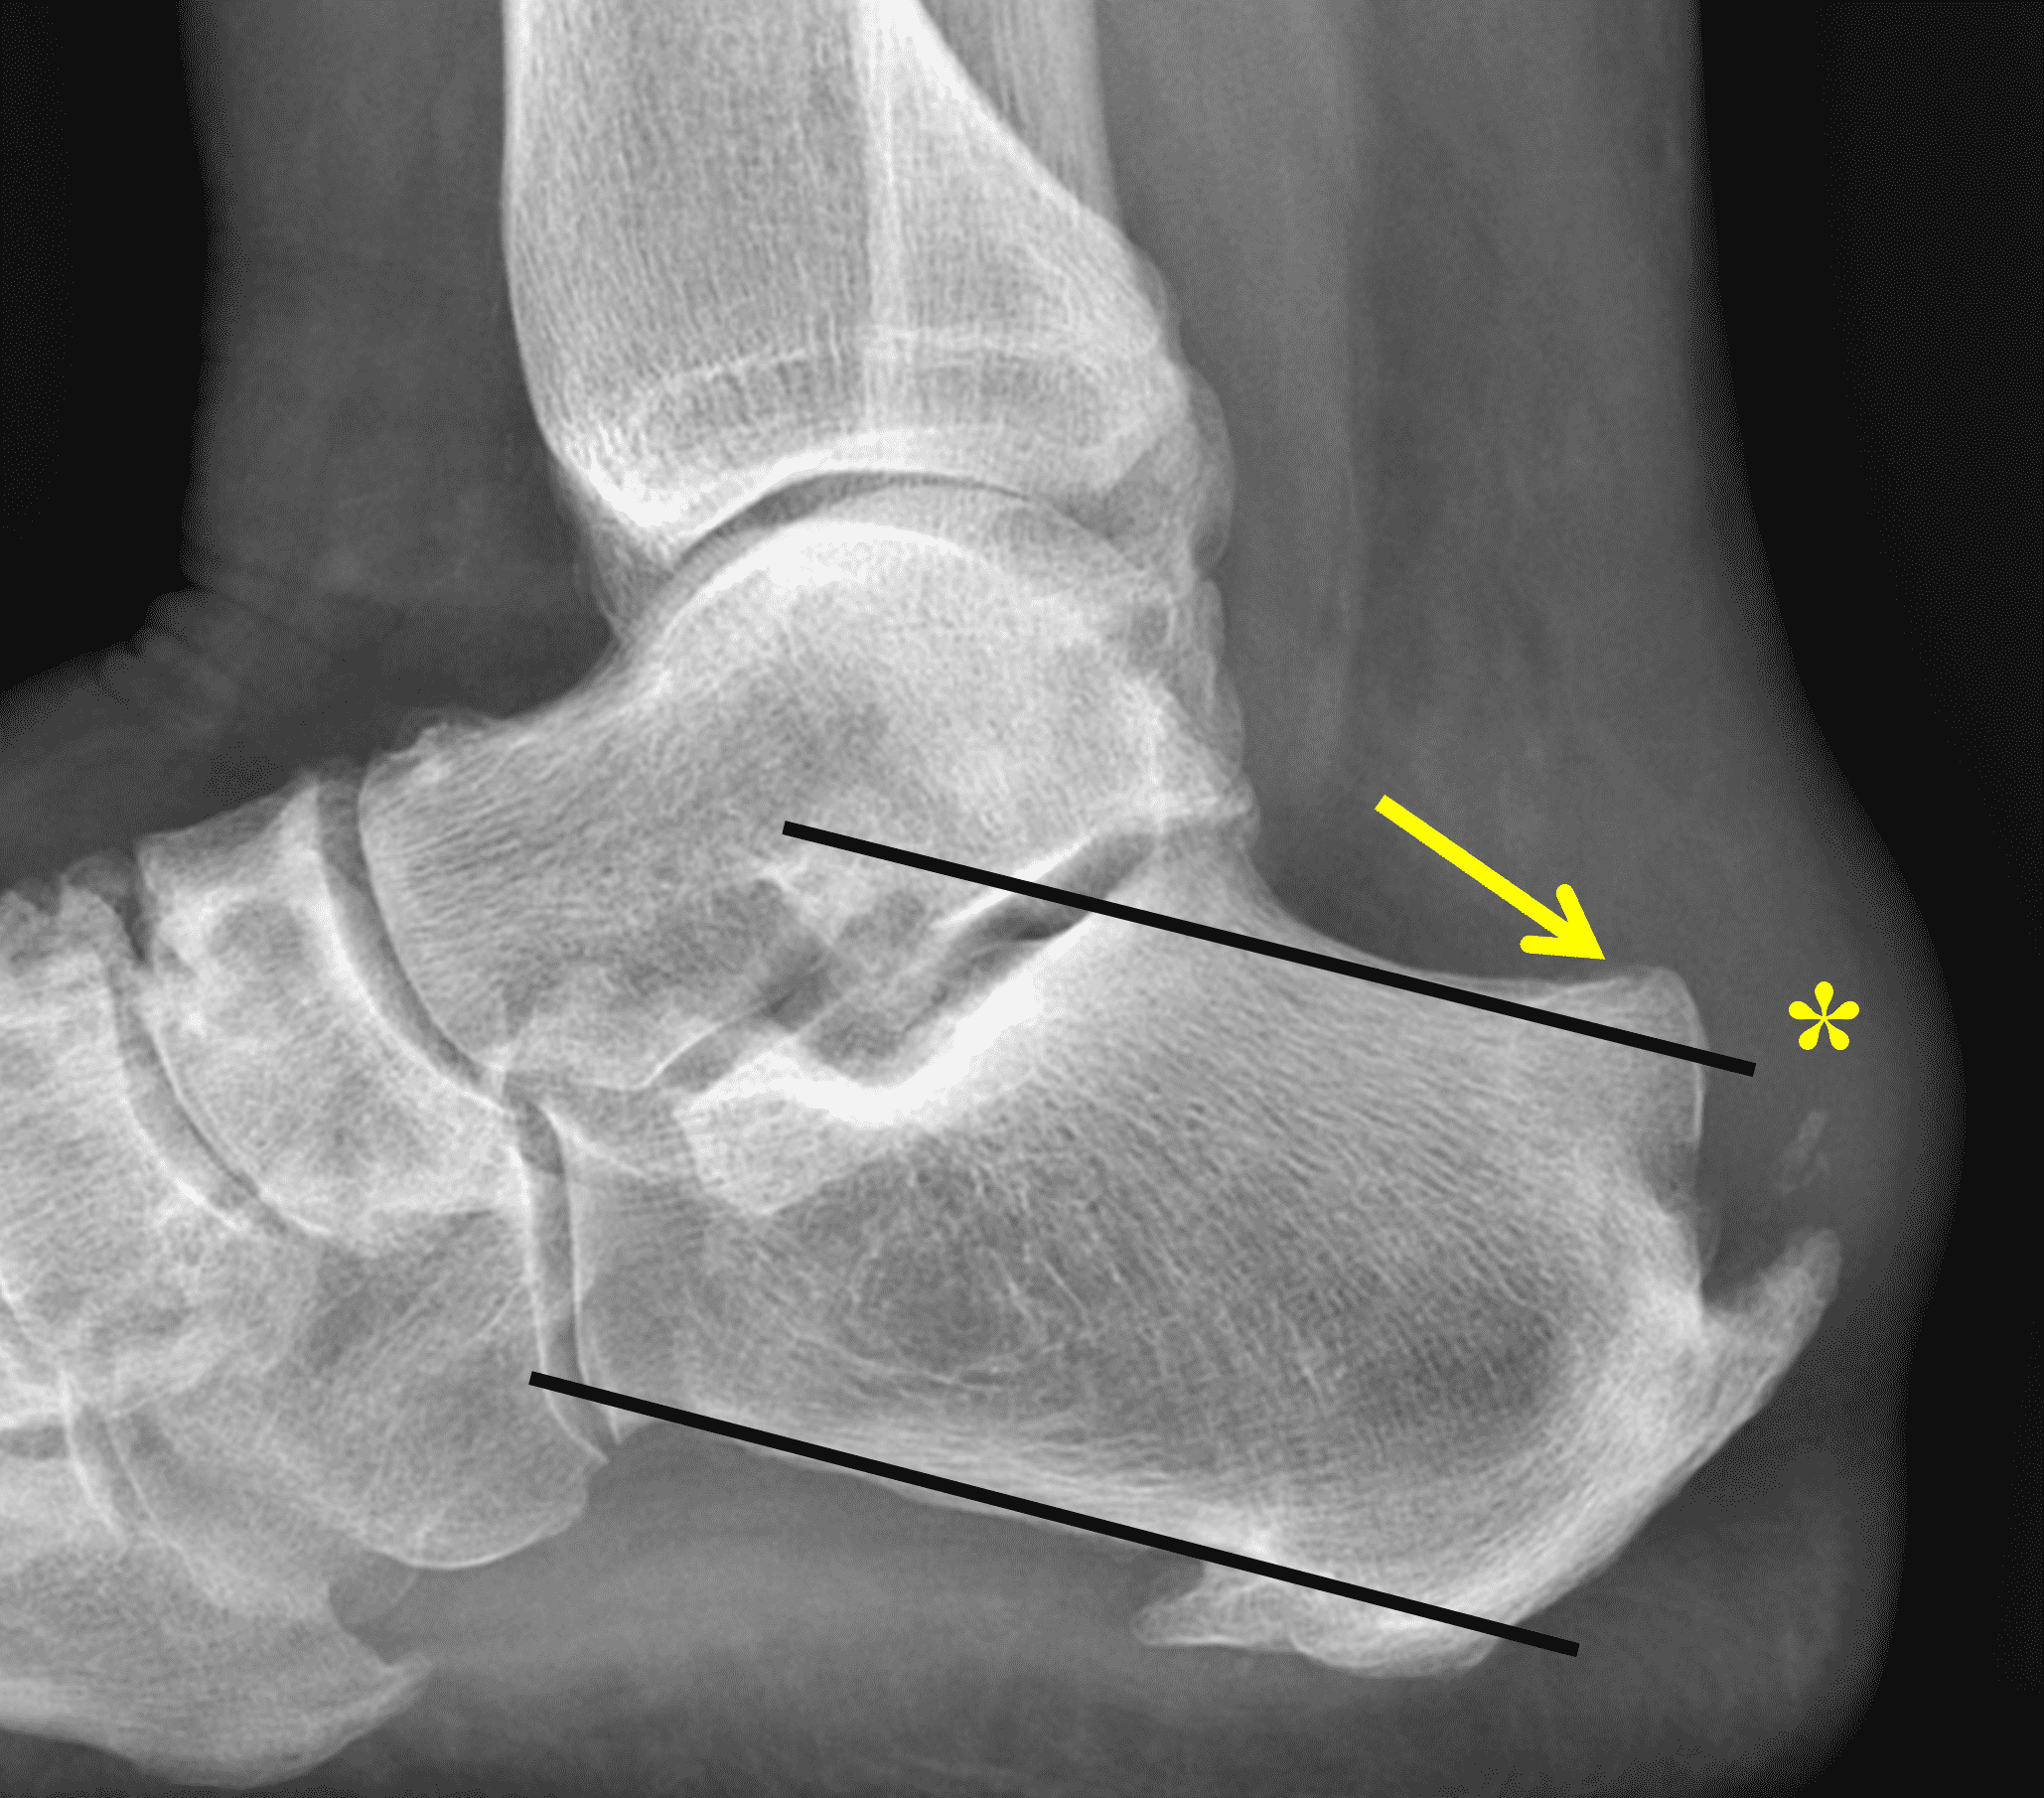

Figure 2: Complete Achilles tendon rupture. (2A) The lateral radiograph shows a thick and indistinct proximal Achilles tendon contour (arrows). (2B) A fat-suppressed T2-weighted image shows complete rupture of the tendon with a fluid-filled gap (yellow arrow) measuring 1.5 cm in length, located 10 cm cranial to the tendon insertion (blue arrow) and just distal to the edematous myotendinous junction (red arrow). The tear is superimposed on diffuse tendinosis. (2C) A sagittal T1-weighted image confirms the diffuse tendinosis. Fluid extends anteriorly into Kager’s fat pad (arrow) suggesting disruption of the anterior paratenon. (2D) A transverse fat-suppressed T2-weighted image through the proximal tendon shows no intact fibers (arrow), confirming the full-thickness rupture.

Figure 5: 69 year-old woman with Haglund syndrome and low-grade insertional Achilles tendon tear. (5A) Lateral radiograph demonstrates a hypertrophied osseous excrescence of the posterosuperior calcaneus (arrow) rising above a pitch line drawn parallel to the inferior calcaneal body. Note the soft tissue swelling (“pump bump,” asterisk) as well as the posterior heel spur and soft tissue calcification. (5B) Sagittal STIR image reveals moderate tendinosis with thickening and increased signal in the distal tendon (arrowheads), mild retrocalcaneal bursitis (red arrow), and the Haglund process with mild adjacent marrow edema (yellow arrow). (5C) Transverse fat-suppressed, fluid-sensitive image shows partial tendon tearing at the calcaneal insertion (arrow). (5D) Post-operative lateral radiograph following resection of the Haglund process and Achilles reinsertion.